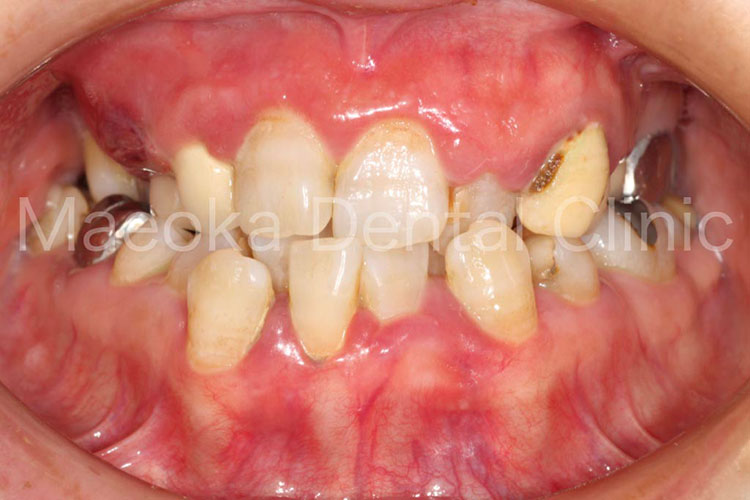

患者さんは49歳女性の方で、「全体的にしっかりと治したい」という主訴で来院されました。

出産を機にお口の環境が悪くなっていったとのことでしたが、勇気が出せずになかなか歯科を受診できなかったそうです。

診査を行うと奥歯の噛み合わせが失われており、審美面、機能面ともに大掛かりな介入が必要な状態でした。

はじめに患者さんから伺った情報を基に、現在の環境になってしまった根本的な原因を模索し、原因除去を行っていきました。その後、歯の移植(右下5を右上3に移植)、部分的な矯正などを行った上で審美的な範囲はセラミックスを用いた被せ物、歯の削除量を最小限にするために見えない箇所は金属を用いた被せ物で最終的な修復を行いました(一部表面的な虫歯は残っていますが、患者さんと相談した上で、今の段階で積極的に削ることは避け、経過観察を行うこととしています)。

プロビジョナルレストレーション(精密な仮歯)を入れた上で機能上問題ないことを確認するなどチェック期間にも時間を要したため、5年に及ぶ治療期間を要しましたが、残りの患者さんの人生の長さを考えると必要十分な治療であったと考えます。

保存不可能と思われる歯が多数ある中ではありましたが、結果として抜歯に至った歯は3本のみで、インプラントを用いることなく、患者さん自身の歯でお口の環境を再構築することができました。

今後はメインテナンスで治療終了時の環境を長期的に維持できるように努めていきます。

治療前(正面)

治療後(正面)